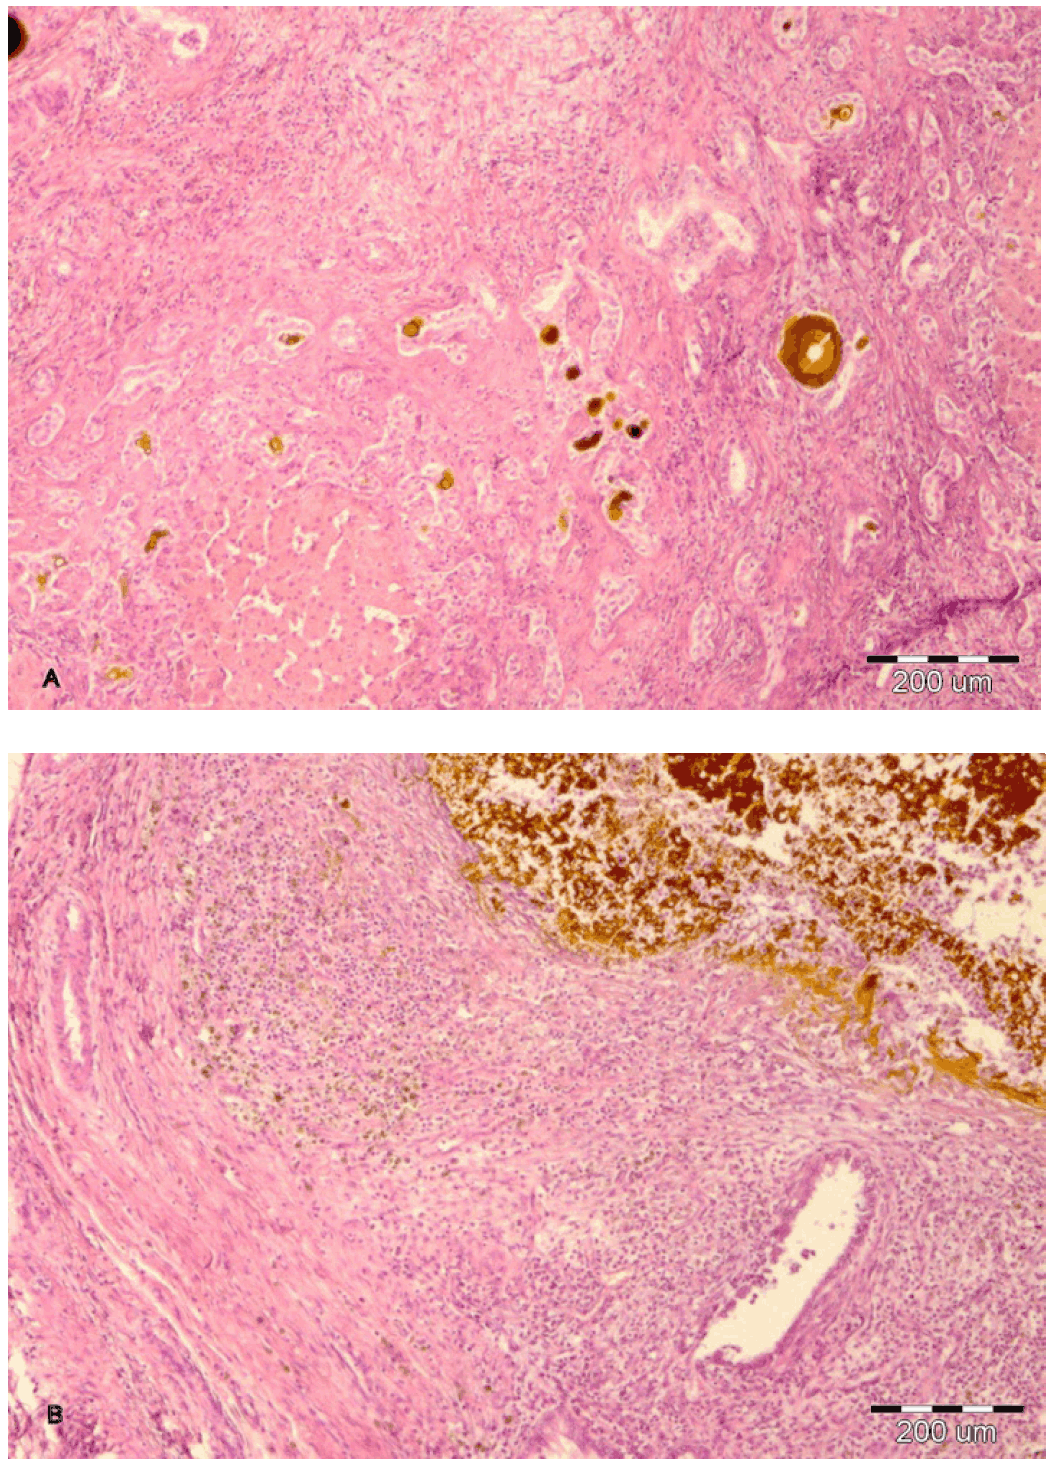

Histopathologic analysis revealed intensive portal fibrosis, numerous ductal plate remnants, hyperplastic and dilated bile ducts with cholestasis and foci of microabscesses (figures 1-3).

Figure 2: A) Portal fibrosis, dilated bile ducts with cholestasis (HE, x40), B) severe inflammatory response around cystic bile duct (HE, x40).